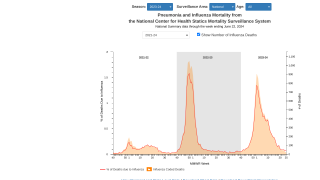

- The proportion of deaths attributed to pneumonia and influenza (P&I) was below the system-specific epidemic threshold in the National Center for Health Statistics (NCHS) Mortality Surveillance System.